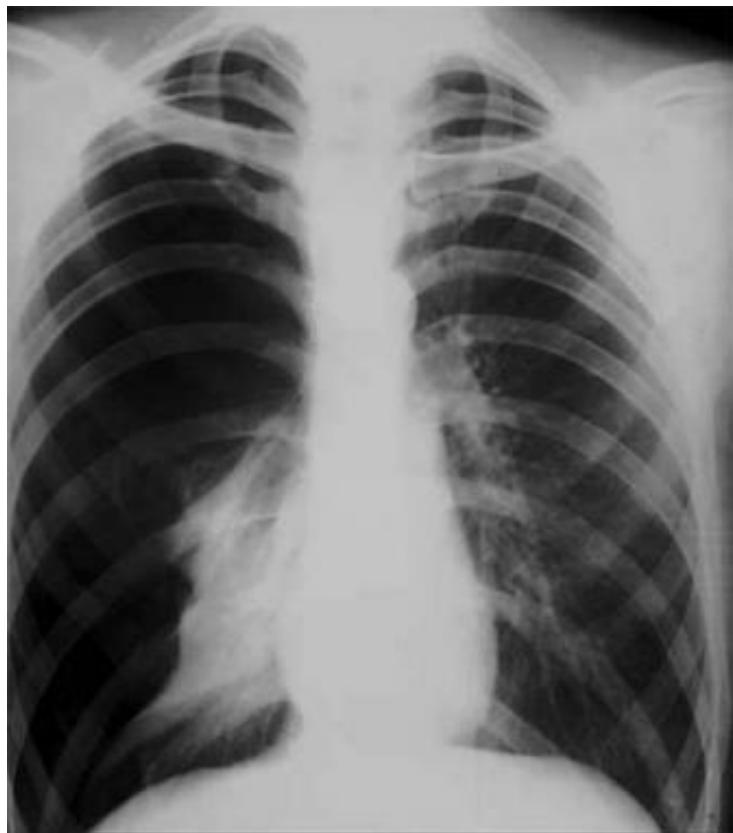

Chest X-ray: Pneumonia

- Finding: Right lower lobe consolidation.